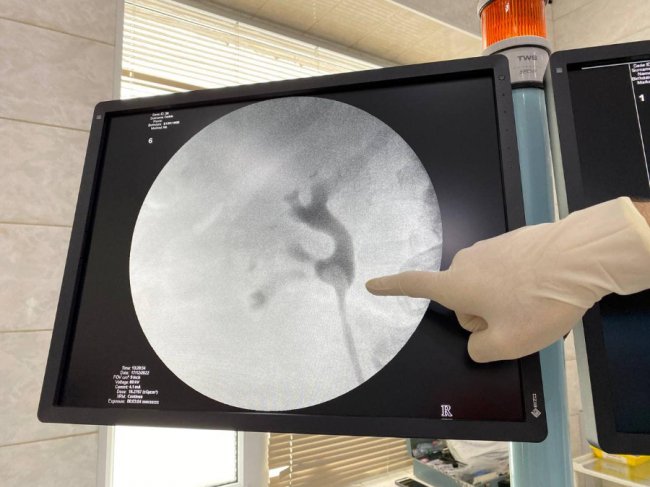

Медики виконали перкутанну нефролітотрипсію - одну з технічно найскладніших операцій в урології. Вона застосовується для лікування сечокам’яної хвороби вже кілька років.

«Лікарі-урологи під контролем рентген-слідкуючої апаратури, через прокол 3 міліметрів в поперековій ділянці, подробили й дістали камінь з нирки. Наступного дня після операції 72-річна пацієнтка повернулася до звичного життя», - розповіли у дописі.